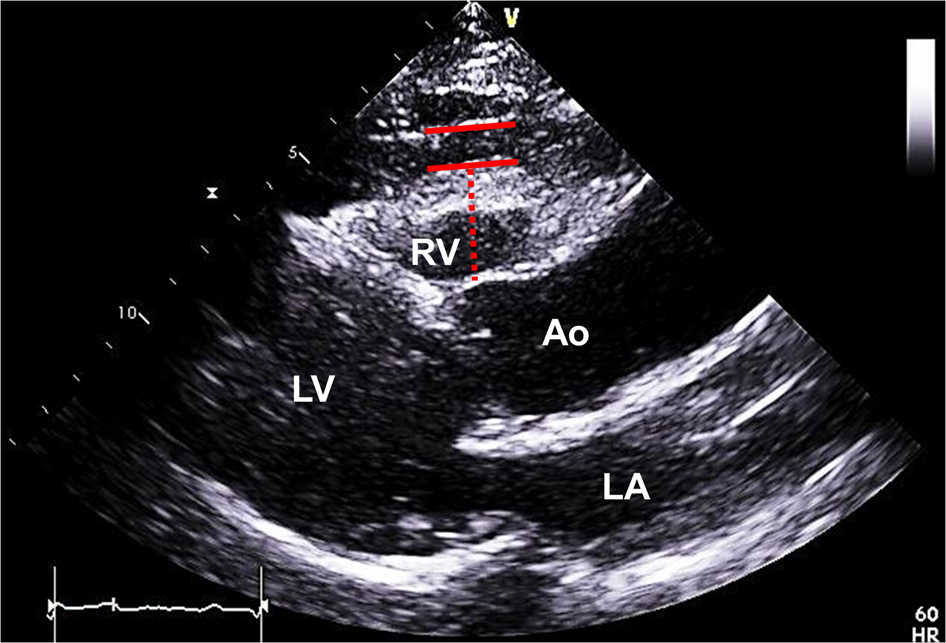

Measurement of EAT thickness using two-dimensional TTE. EAT was defined as the echo-free space between the outer wall of the myocardium and the visceral layer of pericardium (between red bars). Measurements of EAT thickness were obtained perpendicular to the RV free wall (red dotted line) at end-systole in three consecutive cardiac cycles. Ao, aorta; EAT, epicardial adipose tissue; LA, left atrium; LV, left ventricle; RV, right ventricle; TTE, transthoracic echocardiography